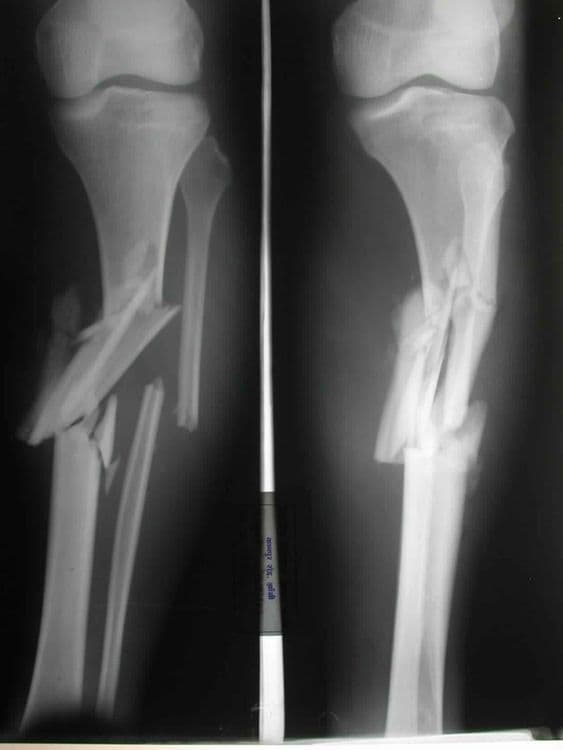

Comminuted Fracture - हाडांचा पूर्णतः चुरा होणे.